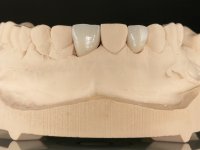

O tratamento iniciou-se com a re -preparação do coto do espigão falso coto fundido, com o objetivo de colocar as linhas de acabamento cervical com uma localização intra-sulcular e simultaneamente confecionar uma coroa provisória adaptada. Com um tratamento ortodôntico muito simples, fechou-se o diastema entre os incisivos centrais superiores e estabilizou-se esta posição com um arame colocado na superfície palatina dos centrais, funcionando como contenção. Posteriormente procurou-se fazer uma tração ortodôntica lenta do dente 2.2 com o intuito de diminuir, ainda que muito ligeiramente a perda óssea vertical nessa zona. Finalizada a tração, foi feita a extração do dente 2.2 e a zona foi reabilitada provisoriamente com uma coroa de resina composta colada aos dentes adjacentes. Foi colocado um implante dentário na zona do dente 2.2 sendo novamente colada a coroa provisória em resina, reabilitando provisoriamente a paciente durante o período de osseointegração. No dente 1.3 foi feita uma gengivectomia com bisturi elétrico, com a intenção de subir o nível cervical do 1.3 conseguindo uma maior harmonia com o dente 2.3. Estabilizados os tecidos moles, foi feita uma impressão com a técnica de moldeira aberta, utilizando silicones de adição de consistência “putty” e “light”. A recolha da cor, tanto da componente dentária como dos tecidos moles foi feita pelo ceramista no consultório.  No laboratório as impressões foram passadas a gesso e deram origem a modelos de trabalho que foram devidamente analisados. Foi decidido confecionar um “abutment” metalo-cerâmico aparafusado sobre o implante. Este “abutment” foi fundido com uma liga nobre e posteriormente revestido a cerâmica coronária e gengival. Dada a inclinação do implante o aparafusamento condicionou de forma inevitável a saída do orifício do parafuso pela superfície vestibular. No sentido de esconder esta situação, o desenho do “abutment” já foi idealizado com a intenção de acomodar na superfície vestibular a colagem de uma faceta feldspática. Este “abutment” foi provado em boca e foram feitos ajustes no componente cerâmico gengival. A sua adaptação aos tecidos moles foi feita tanto de forma subtrativa, com broca, como de forma aditiva, acrescentando resina composta de tonalidade gengival. Este acrescento de resina seria orientador do ceramista na colocação final da cerâmica de tonalidade gengival. A coroa que reabilitaria o dente 1.3 foi cimentada nesta consulta de prova com cimento de ionómero de vidro reforçado com resina composta. Finalizado o trabalho em laboratório da faceta sobre o 1.2 e o “abutment” e a faceta para o implante este foi colado em boca, após a colocação do isolamento absoluto. O trabalho satisfez plenamente a paciente. Durante oito anos a paciente foi seguida regularmente, mostrando-se agradada com o tratamento efetuado, no entanto começou a mostrar interesse em intervir esteticamente nos incisivos centrais superiores. Decidida a segunda fase da nossa intervenção, foi feita a preparação dentária dos dentes 1.1 e 2.1 para a colocação de duas facetas feldspáticas. Particular cuidado foi tido na preparação inter-proximal distal junto ao “abutment” do implante. Foi preciso avaliar muito pormenorizadamente o eixo de inserção da faceta em relação ao “abutment”. As facetas feldspáticas foram confecionadas em laboratório e posteriormente coladas em boca após a colocação de isolamento absoluto. Um ano após, iniciamos a nossa terceira fase de tratamento, após a faceta colada no dente 2.1 ter fraturado. A preparação dentária foi feita sobre a faceta colada, procurando estender mais para palatino o interface inter-proximal distal. O objetivo seria passar para mais palatino do ponto de contacto o interface faceta-dente. O preparo dentário do dente 1.2 também foi muito reduzido, limitando-se a criar um eixo de inserção. Após confecionadas a coroa total e a faceta em laboratório foram coladas em boca. Primeiro foi colada a coroa utilizando-se um isolamento relativo com teflon, posteriormente foi colada a faceta após a colocação do isolamento absoluto. Na coroa utilizei este tipo de isolamento para evitar a utilização de grampos. Seria difícil de aplicar pela forma e dimensão do dente e agressivo para os tecidos moles. Após a colagem foi avaliada a integração oclusal do trabalho.